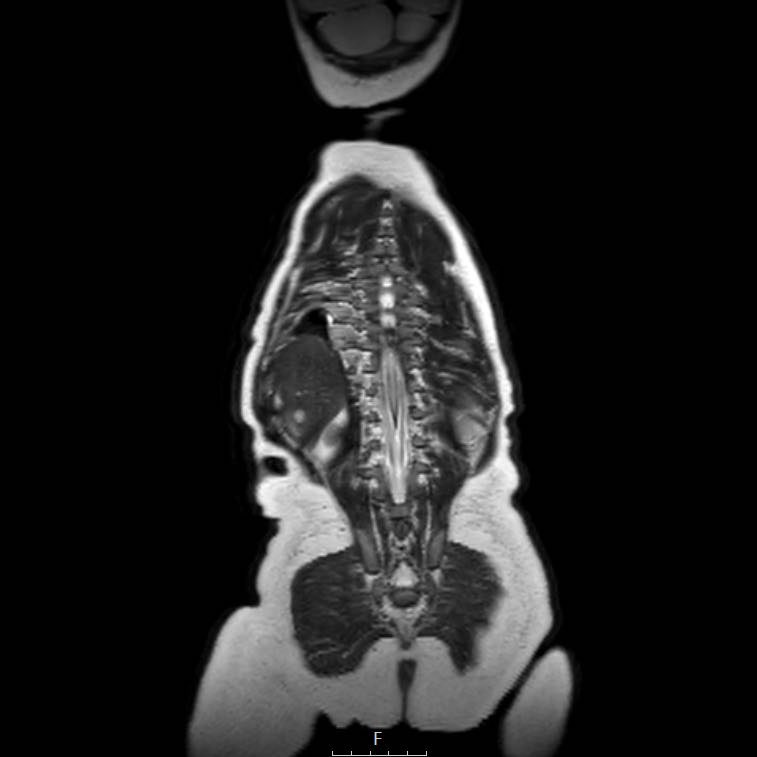

Cuộn qua chuỗi ảnh T2 theo mặt phẳng coronal.

Nghiên cứu các hình ảnh và sau đó tiếp tục đọc.

The findings are:

- Mass with encasement of the aorta and splanchnic vessels.

- Lan rộng dọc theo cột sống ngực nhưng không xâm lấn vào ống sống.

- Small liver metastases.

- Left supraclavicular mass.